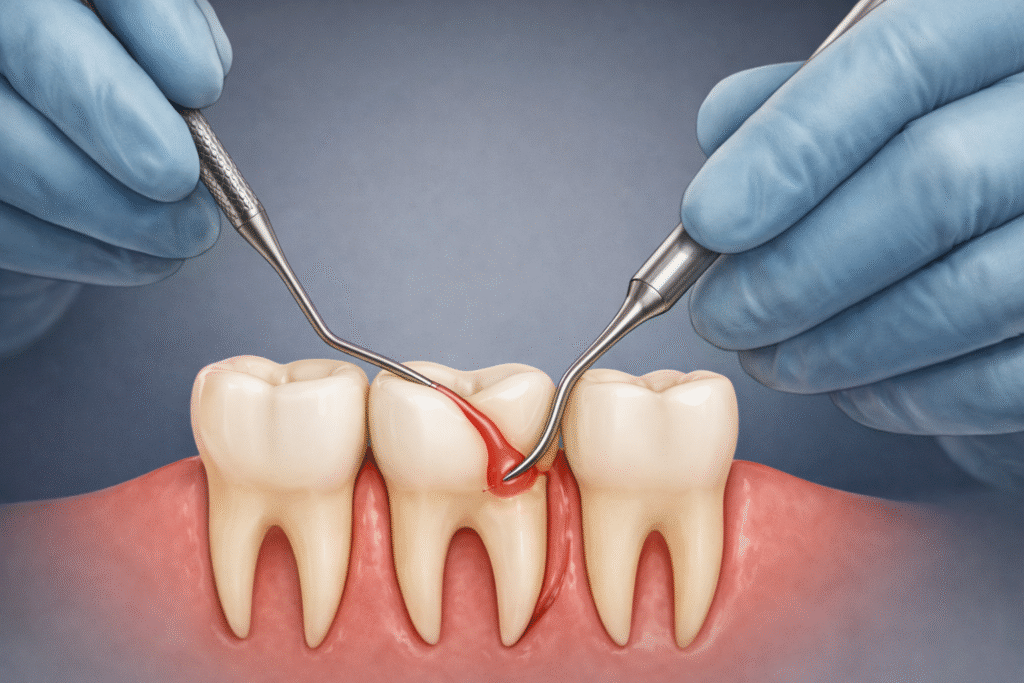

Periodontics (Gum disease) is the most common cause of total teeth loss and need for denture. Firstly, gingivitis and periodontitis can cause gum inflammation, receding gums, tooth mobility, and even tooth loss if left untreated. Therefore, the trick is prevention: from progression, by early detection and treatment. The treatment involved may vary from normal scaling to open flap debridement. Moreover, the aim of all of these treatments in our dental clinic in Pandalam and Pathanamthitta is to remove the harmful calculus and plaque, which would, in turn, minimize the count of harmful bacteria in the mouth. Share A Smile provides various treatments to protect your gums.

Supra Gingival Scaling-We remove the calculus above the margin of gums and attach it to the teeth surfaces in SupraGingival Scaling. Additionally, we use piezotronic and ultrasonic scalers to minimize the discomfort and gain maximum results. Also, you should get regular dental checkups and clean your teeth like a healthy person with no or minimal gingivitis.

Sub Gingival Scaling–Here, the calculus below the margin of gums attached to teeth root surfaces is removed manually or mechanically. Furthermore, the periodontist at our center does all these procedures for patients with mild to moderate levels of gum disease.